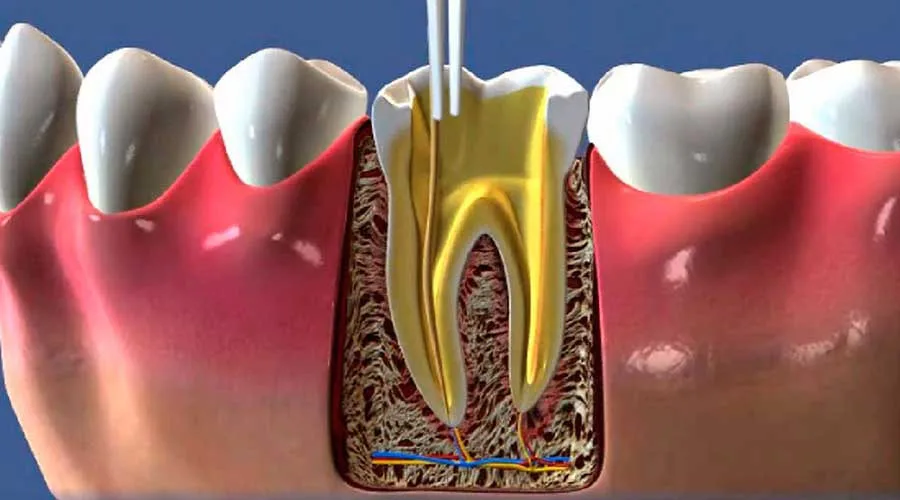

Uma unidade focada nessa especialidade oferece procedimentos de qualidade superior. Isso ocorre devido à prática constante do profissional em lidar com anatomias complexas e casos que exigem rigor técnico:

Limpeza profunda e desinfecção minuciosa dos canais radiculares;

Vedação interna realizada com materiais biocompatíveis de excelência;

Aplicação de métodos que visam a eliminação total de focos infecciosos.

O atendimento em uma unidade preparada é muito mais individualizado. O cirurgião avalia cada caso de forma exclusiva, resultando em um plano de ação adaptado às particularidades biológicas de cada arcada atendida.

Além disso, o uso de recursos atuais promove maior segurança nos processos. Equipamentos modernos auxiliam na realização de diagnósticos ágeis, fundamentando intervenções que respeitam a integridade dos tecidos bucais do paciente.

Contar com o amparo de quem estuda profundamente a polpa dental traz vantagens nítidas para o paciente. O conhecimento aprofundado do especialista é o segredo para um sorriso funcional e livre de dores persistentes:

Diagnóstico exato: essencial para determinar a conduta clínica ideal e evitar complicações;

Abordagem minimamente invasiva: reduz o desconforto e favorece uma cicatrização acelerada.

O especialista sabe como conduzir o tratamento de canal de maneira suave, desmistificando o receio comum a esse tipo de sessão. O foco é salvar a estrutura original do dente, protegendo a harmonia e a mastigação.